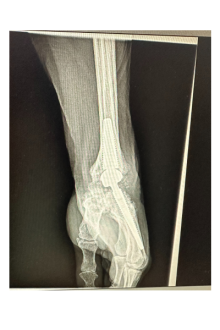

Pose de la 1ère prothèse de poignet de Roanne

Le Dr Ramy Belhaouane, chirurgien orthopédiste spécialiste du membre supérieur, pose la première prothèse de poignet de Roanne chez une patiente âgée de 63 ans.

L’intervention nécessite un geste chirurgical précis dont la durée varie entre 1h et 1h30 et peut se réaliser en ambulatoire. Le chirurgien vient remplacer les os du carpe par une prothèse afin de restaurer une certaine mobilité articulaire.